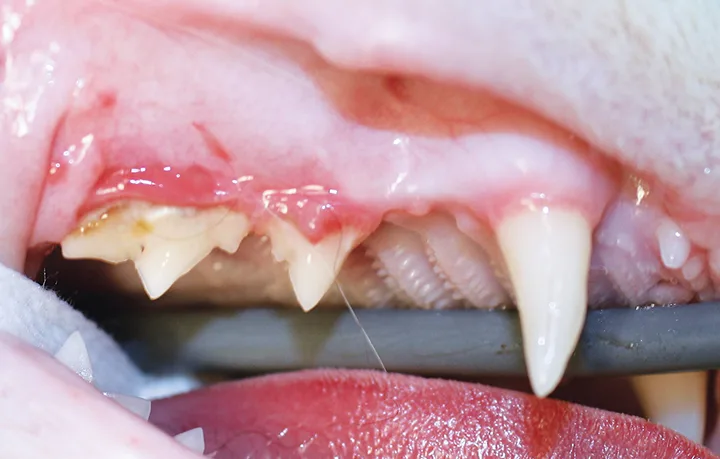

Close-up, lateral image of right cat maxilla.

FIGURE 1

Significant alveolar and labial/buccal mucositis, likely associated with advanced periodontal disease, in a 5-year-old neutered male domestic shorthair cat. Radiographs are recommended to evaluate for any changes (eg, tooth resorption).